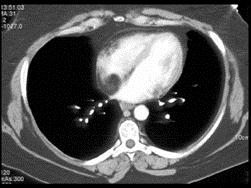

问题 女,35岁,心前区不适,无发热及呼吸困难,请结合CT图像,提出最可能的诊断 ( )

选项 A.脂肪肉瘤 B.脂肪瘤 C.心包憩室 D.心包囊肿 E.心包脂肪垫

答案 B